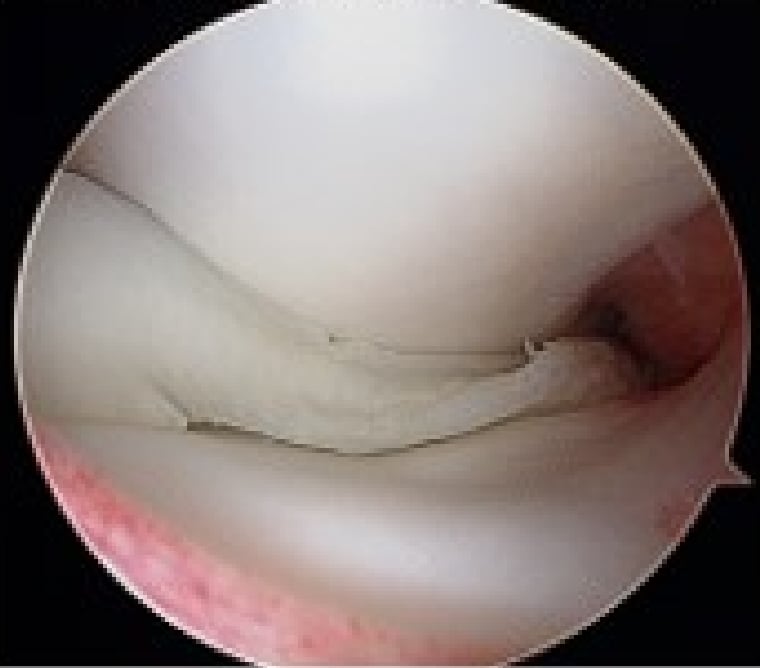

半月板損傷 → 鏡視下半月板縫合/切除

可能な限り縫合することにより半月板を残す方針で治療を行っています。

断裂して変形している

血餅挿入(治癒促進)

縫合後